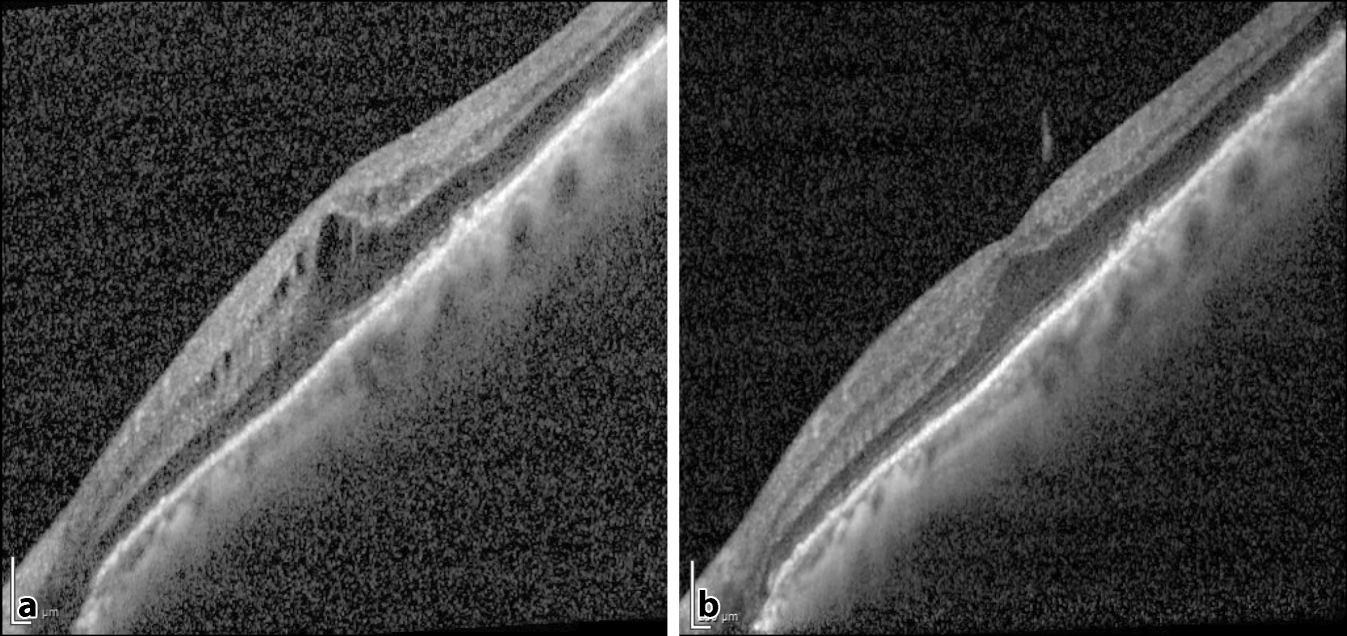

Abb. 3

Vorderabschnitts-OCT: a 1 Tag postoperativ, b 7 Wochen postoperativ

Die Vorderabschnitts-OCT-Untersuchung bestätigte den klinische Befund einer noch ödematösen Hornhaut mit Descemet-Falten (Abb. 3a). Wir vermaßen den Abstand zwischen IOL und Iris, der im Bereich des Irisdefektes bei 11 Uhr 666 µm und bei 5 Uhr 958 µm betrug. Der Abstand zwischen IOL-Vorderfläche und Hornhautrückfläche betrug 4,2 mm.

Sieben Wochen nach der Operation fand sich ein Visus von 0,4, eine zentral klare Hornhaut mit lediglich bei 5 und 6 Uhr leichtem Restödem peripher (Abb. 2d und 3b), weshalb wir die Lokaltherapie weiter reduzieren konnten. Auch das Makulaödem zeigte sich unter der topischen Nepafenac-Therapie (1 mg/ml 3‑mal täglich) rückläufig (Abb. 1b), sodass wir diese auf 2‑mal täglich reduzieren konnten.